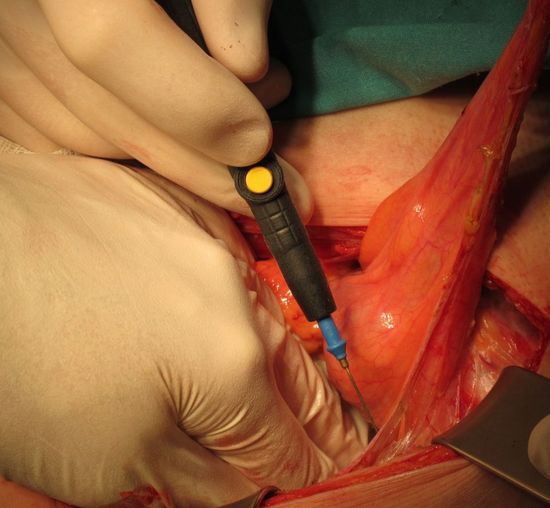

ФОрмирования анастомозов между мочеточниками и недетубулиризированным участком необладера

Наложены провизорные швы на уретру